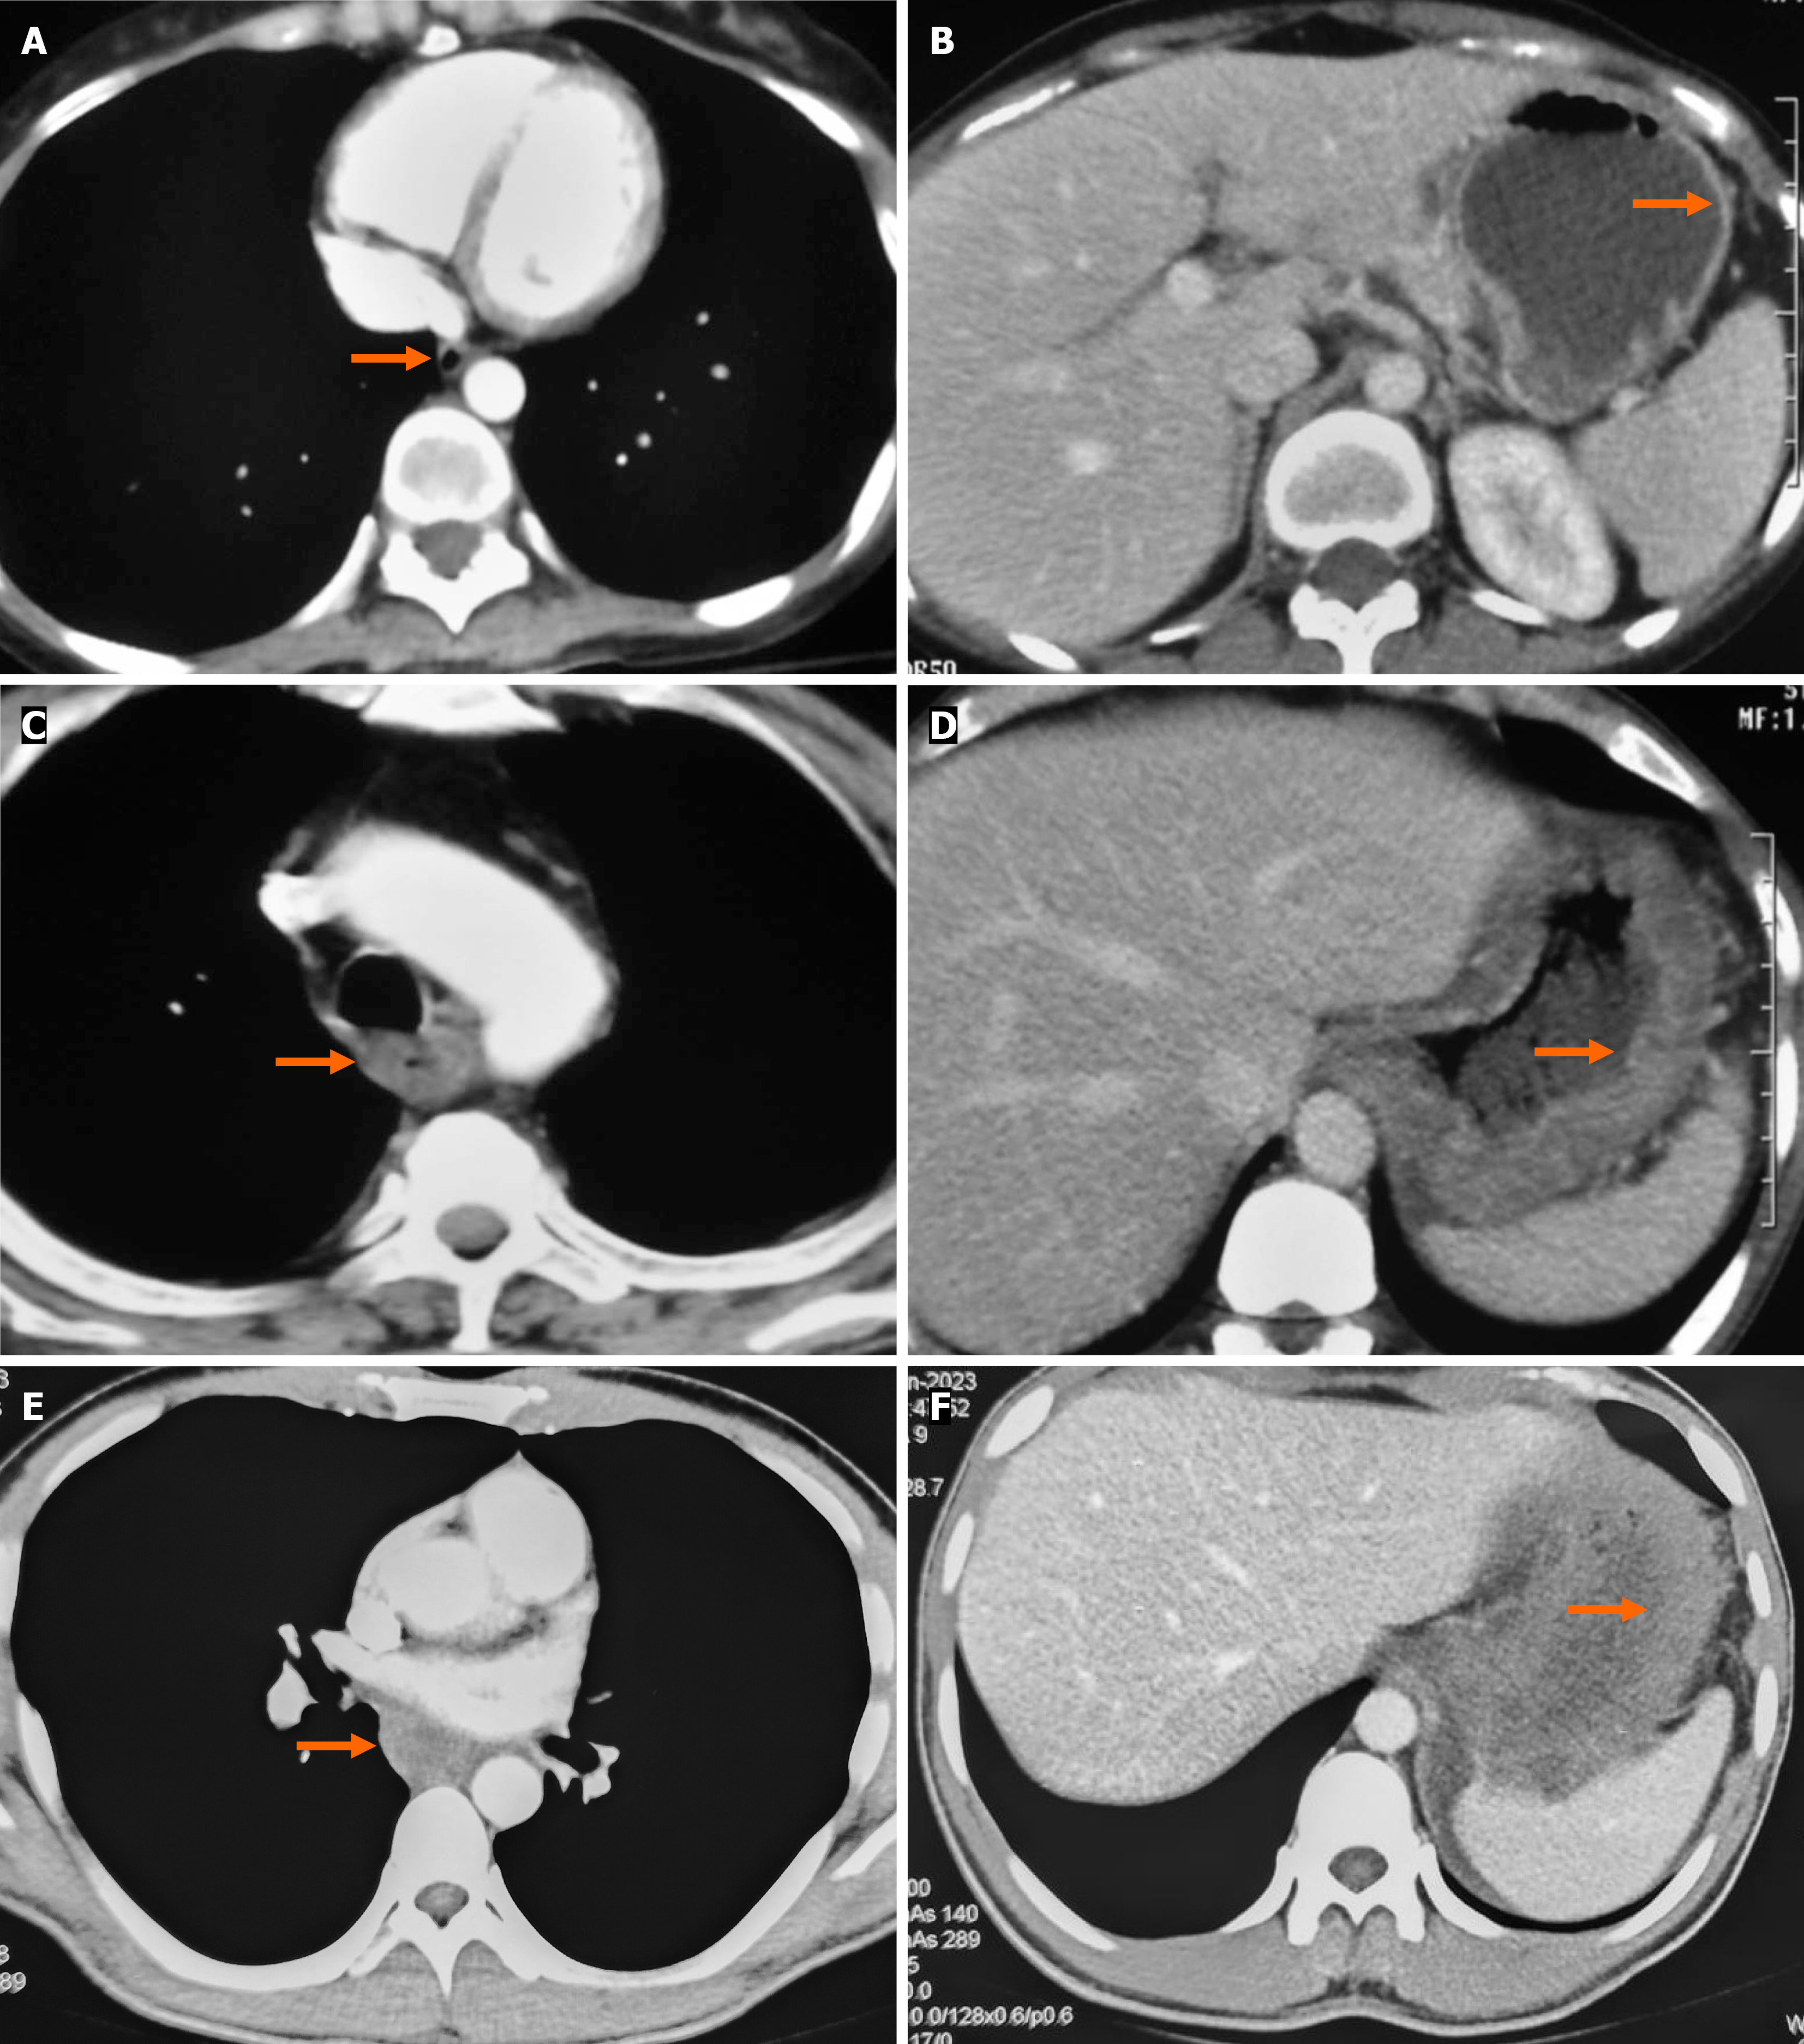

CT grading systems in caustic injury: Several CT-based grading systems have been proposed to standardize the radiological assessment of caustic injuries, the most commonly cited being those by Ryu et al[5] and Chirica et al[7] The Ryu system is a 4-point classification based on esophageal wall thickening and peri-organ collections, with additional assessment of surrounding tissue infiltration and inflammation (Table 2). In contrast, the Chirica system is a simplified 3-point classification that evaluates wall thickening and enhancement, while also incorporating peri-visceral inflammatory changes (Table 2 and Figure 3). The Chirica grading is versatile, as it can be applied to the esophagus, stomach, or other hollow organ, whereas the Ryu grading is specific to esophageal injury. Both systems are useful in predicting stricture development of the esophagus, but Chirica grading also provides valuable short-term prognostic information, including the likelihood of intensive care unit admission and surgical exploration in cases of impending perforation[7].

| Chirica classification | ||

| Grade 1 | Normal appearing GI tract | No injury |

| Grade 2 | Wall edema, surrounding soft tissue inflammation and increased postcontrast wall enhancement | Mild to moderate risk of injury; moderate to high risk of stricture formation |

| Grade 3 | Transmural necrosis, as shown by the absence of postcontrast wall enhancement with surrounding soft tissue inflammation | Moderate injury; risk of stricture formation; close monitoring required |